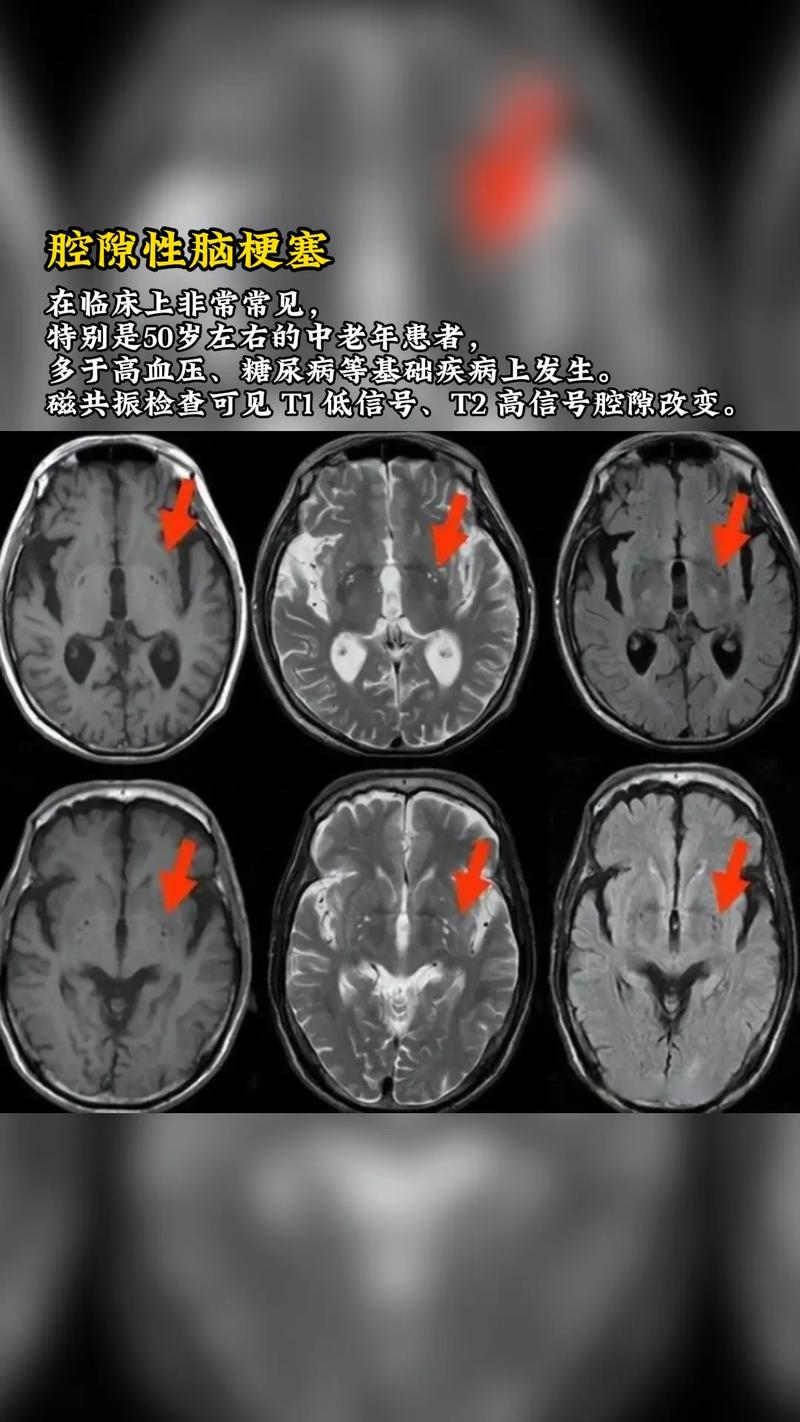

- 超早期(时间窗极短):MRI技术非常先进,有多种序列(DWI、FLAIR、T2WI等)能极早发现缺血性改变。

- DWI (弥散加权成像):这是诊断超早期脑梗死的“金标准”,在脑缺血发生后的几十分钟到2小时内,由于细胞毒性水肿导致水分子扩散受限,DWI序列上就会出现高信号(亮斑),在常规的CT或MRI序列上可能还完全看不出来。

- FLAIR (液体衰减反转恢复) 和 T2WI (T2加权像):在DWI显示高信号后几小时,这些序列上也会逐渐出现高信号。